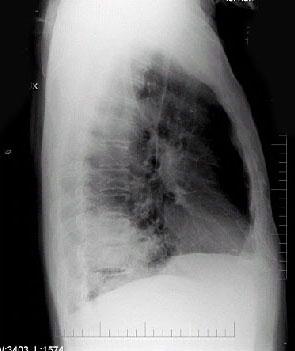

男性,62岁,咳嗽、胸痛1月,X线检查如图,最佳的诊断是 ( )A.右下肺炎症B.右下肺不张C.右肺癌D.右肺转移瘤E.右胸腔积液

问题 男性,62岁,咳嗽、胸痛1月,X线检查如图,最佳的诊断是 ( )

选项 A.右下肺炎症 B.右下肺不张 C.右肺癌 D.右肺转移瘤 E.右胸腔积液

答案 C